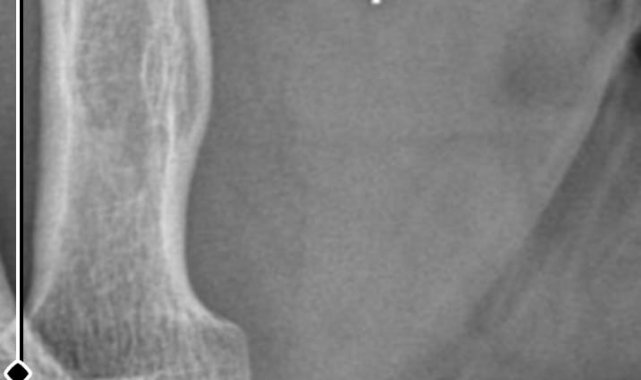

Öte yandan, ameliyatların ardından ağrıları devam eden Güleryüz'ün kolunda metal parça bulunduğu ve bu parçanın parmak bölgesinden dirseğe doğru ilerlediği öne sürüldü. Ayrıca, fabrikada temizlik personeli olarak çalışan Nurettin Güleryüz'ün hastane sürecinde işten çıkarıldığı da öğrenildi.

"Doktorlara bileğime doğru ağrılarım olduğunu sürekli ifade etmeme rağmen beni dinlemediler. Sonradan kolumda metal kaldığını öğrendik. Bunun ihmal olduğunu düşünüyoruz. Çünkü kola metal nasıl girebilir? Ben 9 aydır çalışamıyorum. Kalp rahatsızlığım sebebiyle yüzde 46 engelliyken şu anda yüzde 75 engelli durumuna düştüm. Erken emeklilik dilekçesi verdim ancak henüz sonuç gelmedi. Bu konuda çok mağdurum. Yetkililerin bunu duymasını istiyorum. Savcılığa suç duyurusunda bulunduk. Yaklaşık 9 aydır henüz soruşturma izni gelmedi. Süreci bekliyoruz, henüz dava açılmış değil. Kolumda bırakılan metal ilerliyor. Pazartesi günü bunun için de operasyon geçireceğim. Çıkarılıp çıkarılamayacağı net değil. Elimde titremelerim var, çalışamıyorum ve işveren tarafından işten çıkarıldım. Yetkililerden destek ve konunun incelenmesini talep ediyorum."